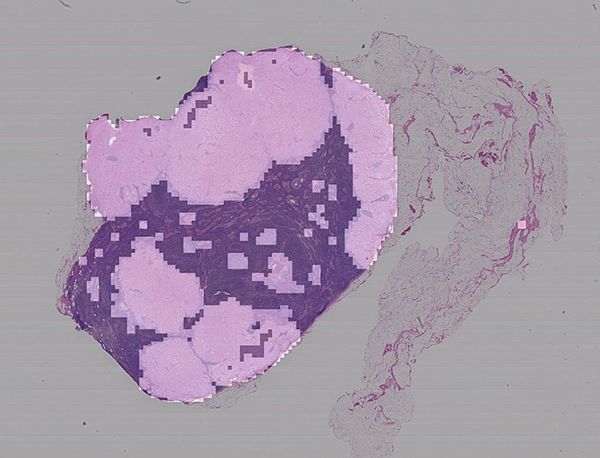

在显微镜载片上,粉红色部分表示神经网络认为的可能是病变的组织。图片来源:史蒂文·弗兰克

使用CNN来分析艺术品的挑战也困扰着医学图像的自动化分析,尤其是病理学家用来分析癌症和其他疾病迹象的大量组织样本的全幻灯片图像(WSIs)。这些图像可能有数十亿像素大小,通常需要在功能强大的工作站上观看,这些工作站可能直接由幻灯片扫描仪集成。目前,人工智能的应用还需要向全尺寸图像努力,研发更专业的硬件,如强大的图形处理单元来进行处理分析。这些努力也受到“黑匣子”问题的影响:如果计算机只是对切片进行分类,病理学家们该如何确定它是否找对了地方?

相对于一个巨大的WSI而言,CNN能分析的最大的切片的大小也是远远不够的。病理学家该如何确定他们可以准确捕捉到那些对诊断至关重要的解剖结构?肿瘤细胞可以熟练地伪装自己,疾病的线索可能潜伏在它们的外部,其形式可能是周围组织的组成变化或附近免疫细胞异常,因此判断性特征并不总是可用于判断的。

图像熵可能会有所帮助。图像缩放和切片大小可以作为“旋钮”,不断调整直到达到分类精度的峰值。训练和测试一系列图像和切片大小,就像我们对绘画作品所做的那样,可以让CNN区分病变和正常组织,甚至是各种形式的疾病。虽然我们已经在用图像熵来确定最具判断力的切片,并用他们来训练我们的神经网络,但在医学领域,以肿瘤为例,以这种方式识别的切片甚至可以在CNN分析之前,以组合的方式提供相当不错的判断。——S.J.F.